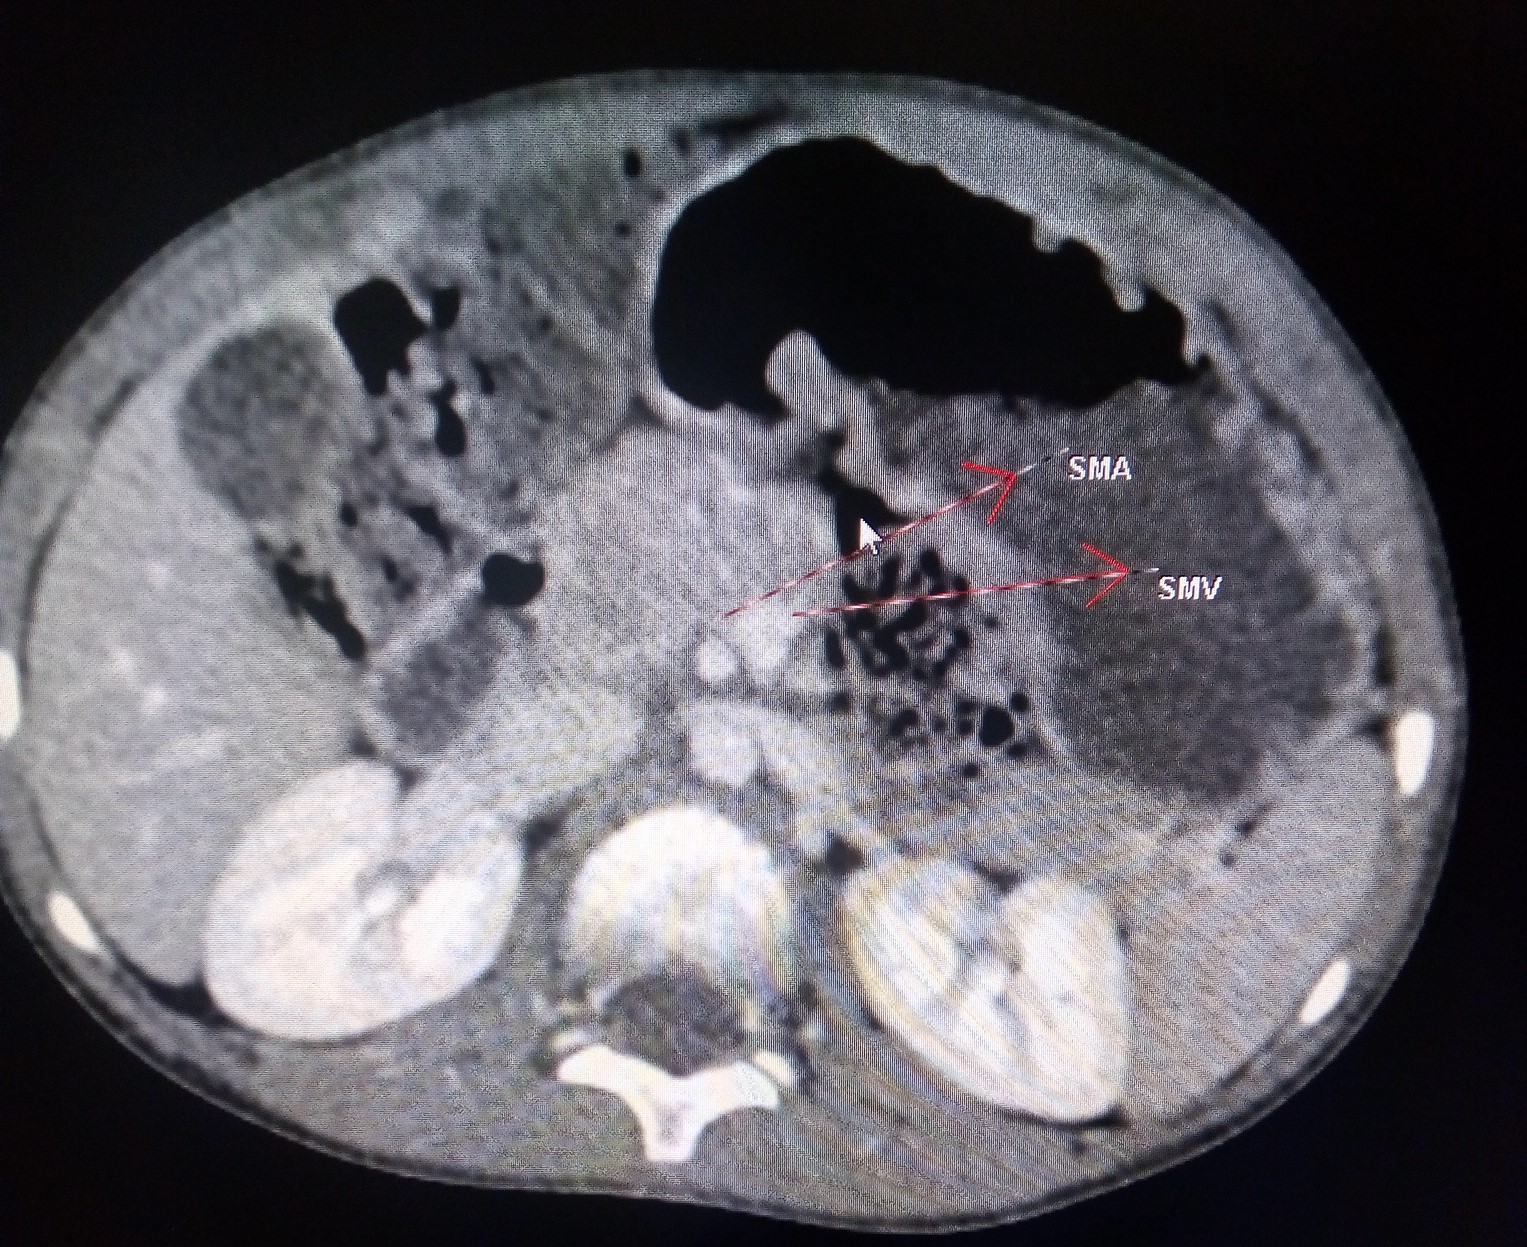

Midgut Volvulus CT Sumer's Radiology Blog Corkscrew Duodenum The corkscrew sign (figure 1b) refers to the twisted configuration of the proximal small bowel loops seen on upper gastrointestinal (ugi) in. In patients with malrotation and volvulus, the. The child may also show a corkscrew effect diagnosing volvulus or complete duodenal obstruction, with the small bowel looping entirely on the right side of the abdomen. Midgut volvulus is a. Corkscrew Duodenum.

Midgut Volvulus CT Sumer's Radiology Blog Corkscrew Duodenum Corkscrew duodenum in malrotation with a midgut volvulus. The helix type appearance of the midgut seen in malrotation with midgut volvulus has been likened to the metallic helix of a. Imaging spectrum of the duodenum on fluoroscopy A corkscrew appearance of the duodenum and proximal jejunum (figure 1) was pathognomonic for midgut volvulus. The corkscrew sign (figure 1b) refers to. Corkscrew Duodenum.